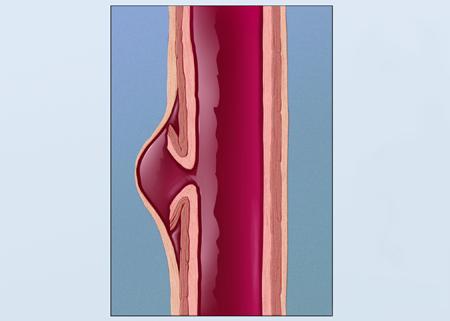

A saccular-shaped aneurysm bulges or balloons out only on one side. A pseudoaneurysm, or false aneurysm, is not an enlargement of any of the layers of the blood vessel wall. A false aneurysm may be the result of a prior surgery or trauma. Sometimes, a tear can occur on the inside layer of the vessel.

A pseudoaneurysm, or pseudoaneurysm of the vessels, occurs when a blood vessel wall is injured and the leaking blood collects in the surrounding tissue. It is sometimes called a false aneurysm. In a true aneurysm, the artery or vessel weakens and bulges, sometimes forming a blood-filled sac.

A pseudoaneurysm, also known as a false aneurysm, is a locally contained hematoma outside an artery or heart due to damage to the vessel wall. The injury goes through all the three layers of the arterial wall causing a leak, which is contained by a new weak wall formed by the products of the clotting cascade.

Pathology. Aortic pseudoaneurysms are contained ruptures of the aorta in which the majority of the aortic wall has been breached, and luminal blood is held in only by a thin rim of the remaining wall or adventitia.